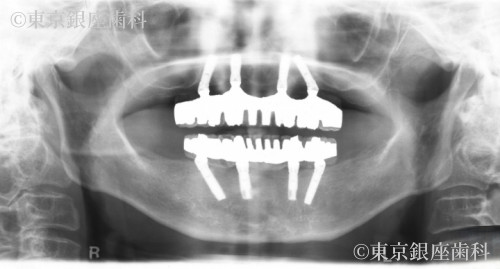

重度歯周病で上下インプラントを選択。治療後、顔の赤みが改善し噛む機能も回復。補綴の形態修正も行い自然で快適な仕上がりに。

上下ワンデイインプラント